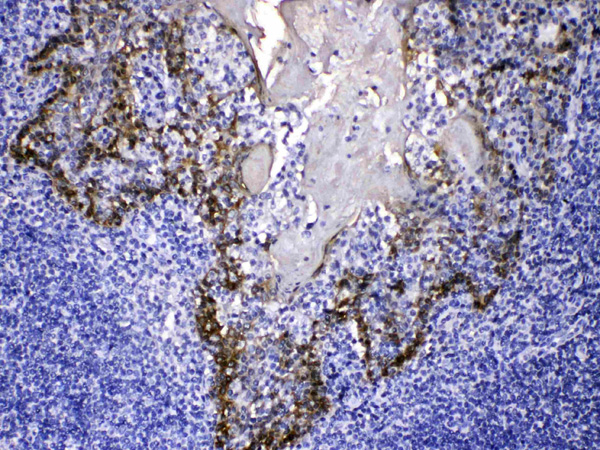

(Cytokeratin 14 was detected in paraffin-embedded sections of human tonsil tissues using rabbit anti- Cytokeratin 14 Antigen Affinity purified polyclonal antibody at 1ug/mL. The immunohistochemical section was developed using SABC method.)

IHC (Immunohiostchemistry)